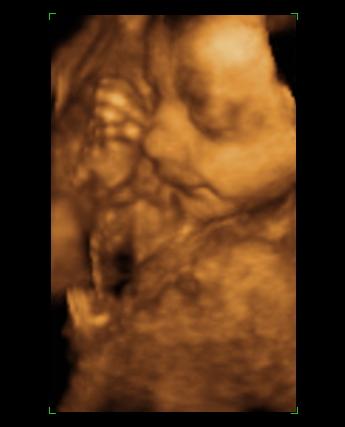

[quote="mpatr"][ írta:mpatrb]Nici, a felvétel élessége és sikerültsége sok mindentől függ.

A profi gépen túl a profi és türelmes szonográfus, a lepény és baba helyzete (mellső fali lepénynél kicsit nehezebb az ügy, meg a babák is imádnak belebújkálni a lepénybe), a magzatvíz mennyisége, a mama hasfalának zsírrétege (mennyire dagi anyuci) szóval ezek (biztos van még) min-mind befolyásolják a felvétel minőségét.

Nekem sikerült ugyanarról a gyerkőcről aki a pocimban van nagyon tuti és nagyon sz..r képet is készíteni ugyanazzal a géppel.

Érdemes többször próbálkozni.